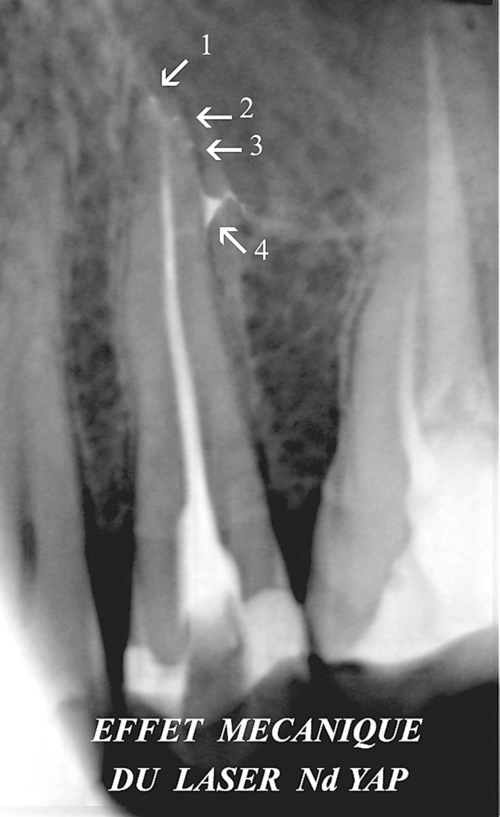

Certains lasers ont un effet mécanique qui permet de pousser les obturations dentaires dans les canaux inaccessibles afin de fermer de manière hermétique toutes les extrémités du réseau canalaire de la racine (fig.14).

fig. 14

Obturation hermétique de 4 canaux latéraux